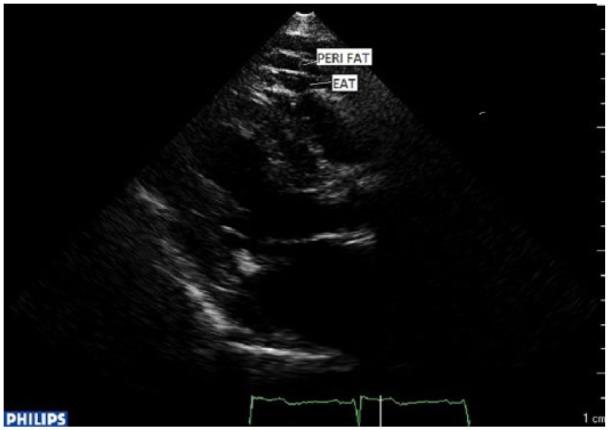

This was a cross-sectional study of 103 atrial fibrillation patients, divided into two subgroups of paroxysmal and permanent atrial fibrillation, and 81 controls, in sinus rhythm. Echocardiography was used for estimation of epicardial adipose tissue and left atrial size and high-sensitivity C-reactive protein, interleukin-6 and adiponectin were measured in all subjects.

方法

这是一项横断面研究,纳入103例心房颤动患者,分为阵发性和永久性心房颤动两个亚组,以及81例窦性心律的对照组。采用超声心动图评估心外膜脂肪组织和左心房大小,并测定所有受试者的高敏C反应蛋白、白细胞介素-6和脂联素。